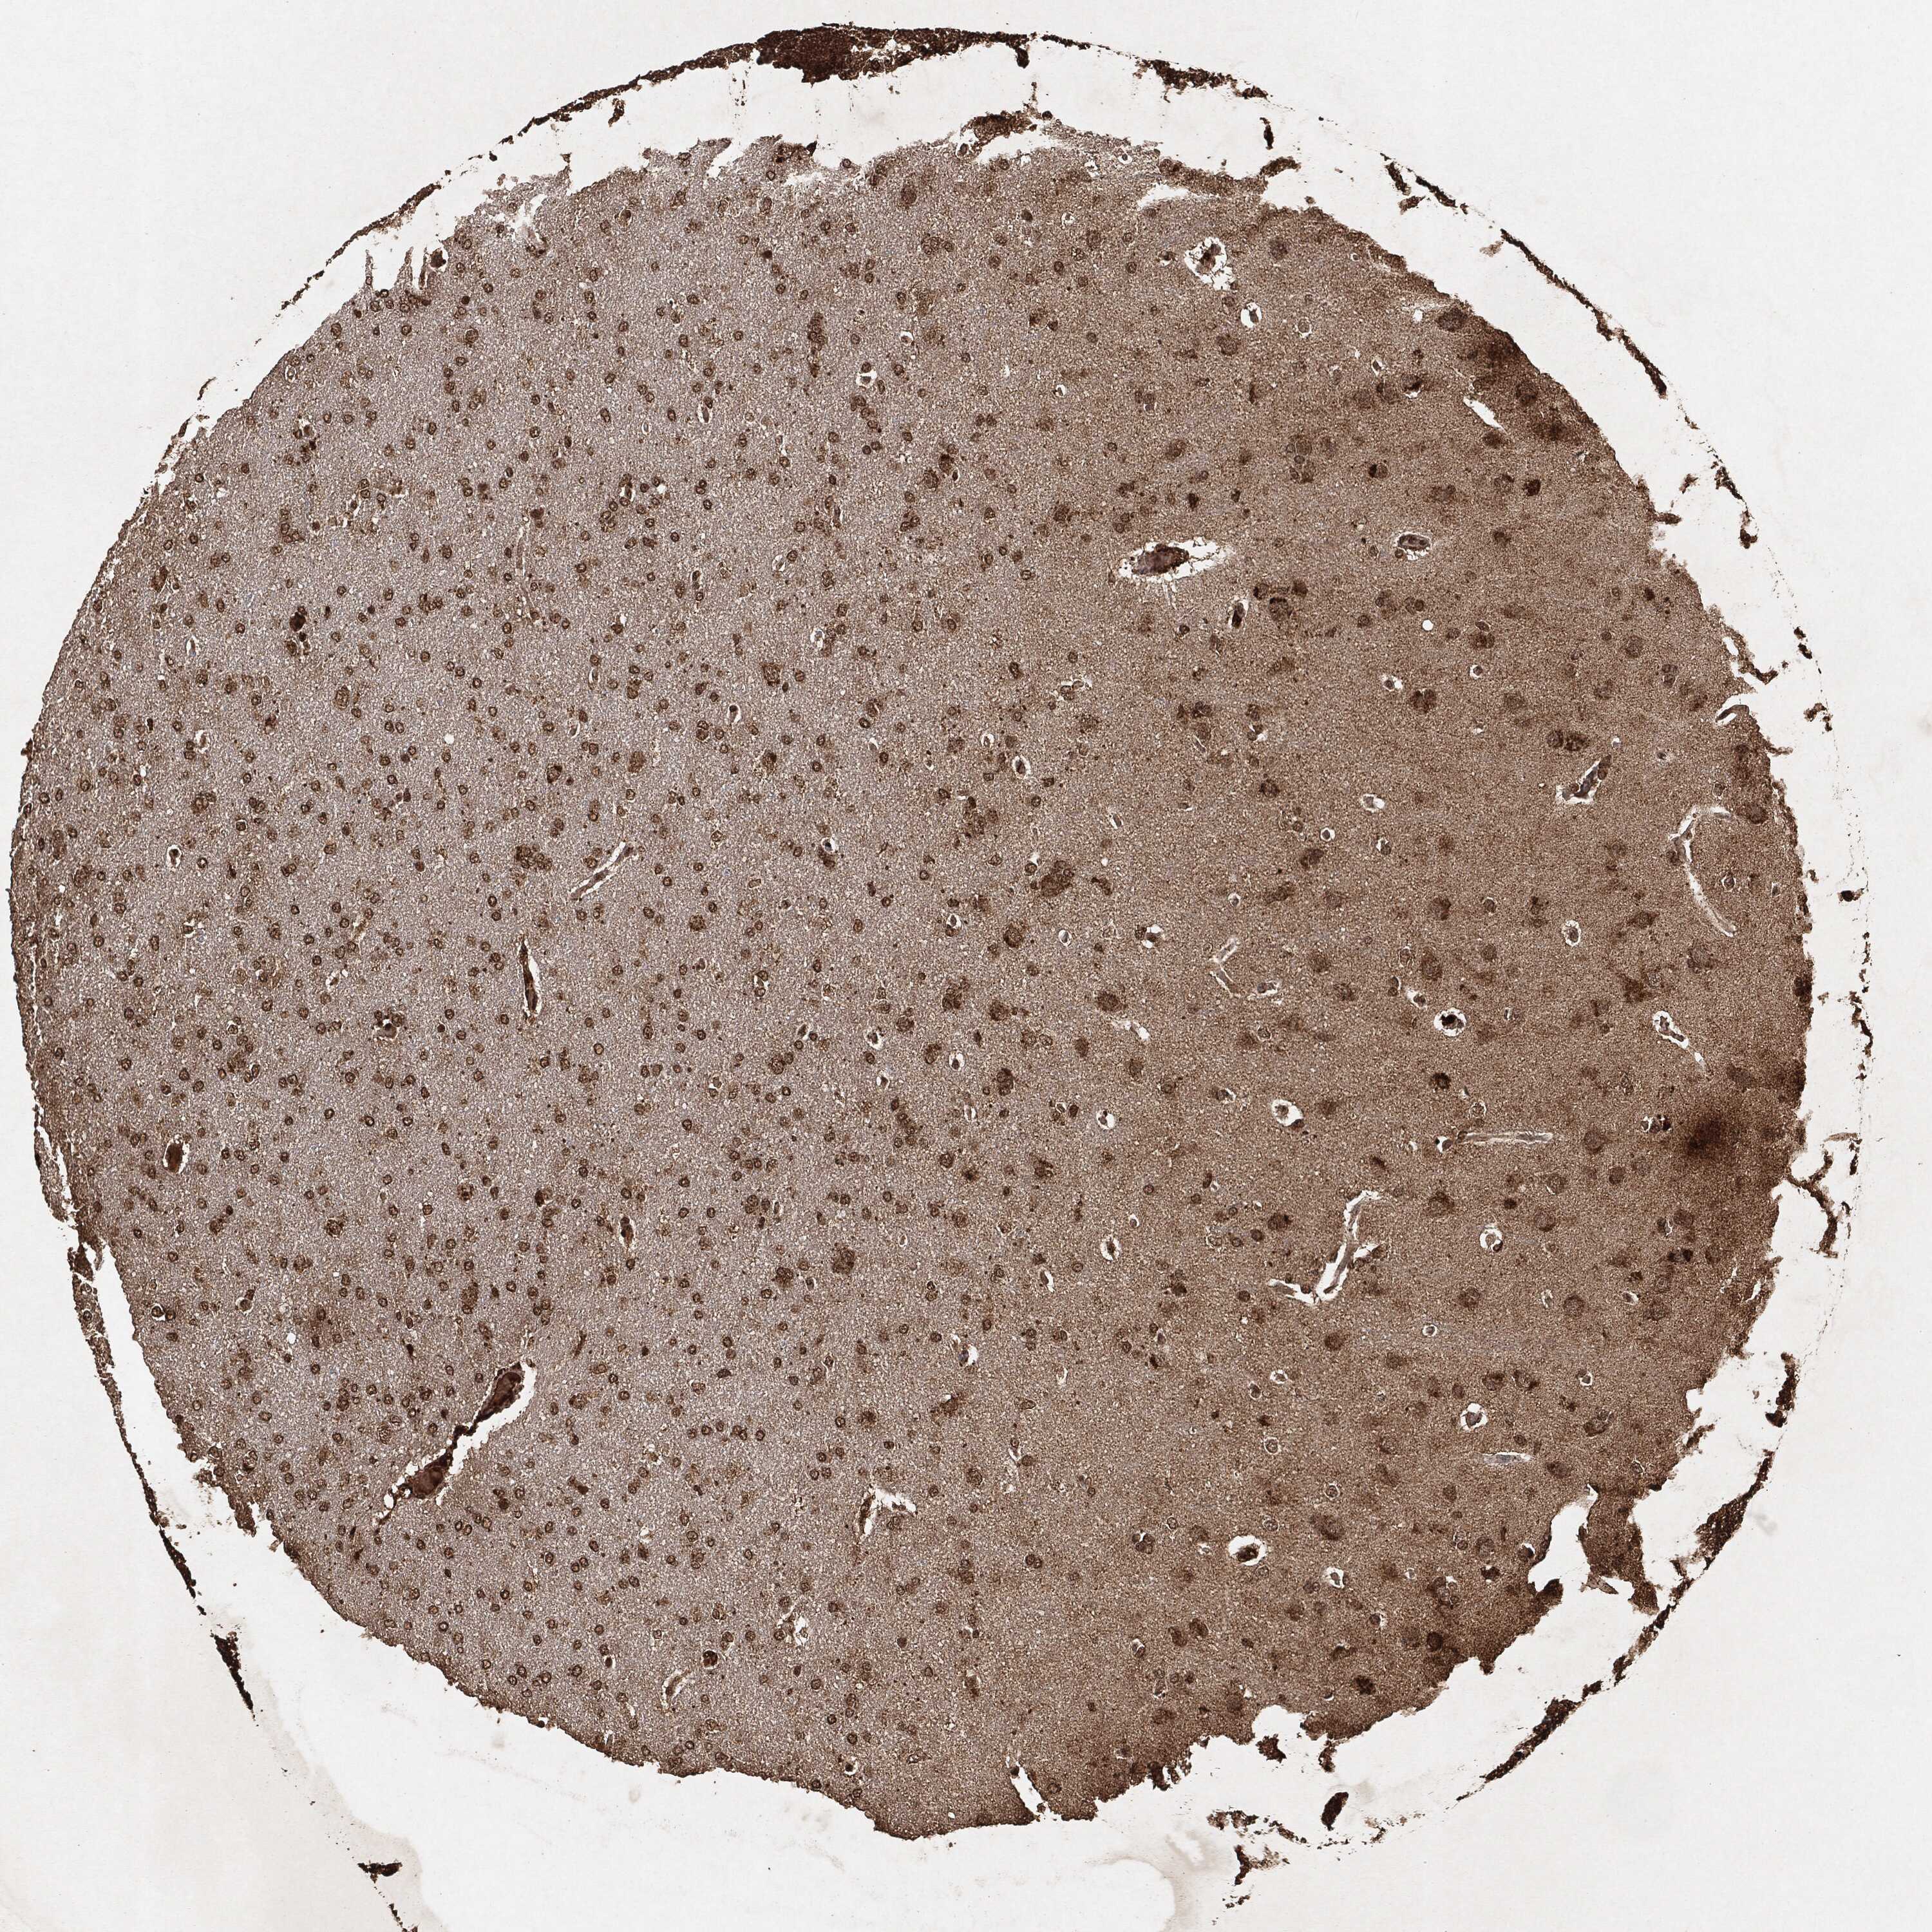

GLIOMA - Protein expressioni

A mouse-over function shows sample information and annotation data. Click on an image to view it in a full screen mode. Samples can be filtered based on level of antibody staining by selecting one or several of the following categories: high, medium, low and not detected. The assay and annotation is described here.

Note that samples used for immunohistochemistry by the Human Protein Atlas do not correspond to samples in the TCGA dataset.

Antibody stainingi

Antibody staining in the annotated cell types in the current human tissue is reported as not detected, low, medium, or high, based on conventional immunohistochemistry profiling in selected tissues. This score is based on the combination of the staining intensity and fraction of stained cells.

Each image is clickable and will lead to virtual microscopy that enables deeper exploration of all samples and also displays staining intensity scores, fraction scores and subcellular localization as well as patient and tissue information for each sample.

Glioma, malignant, High grade

Glioma, malignant, Low grade

Glioma, malignant, NOS